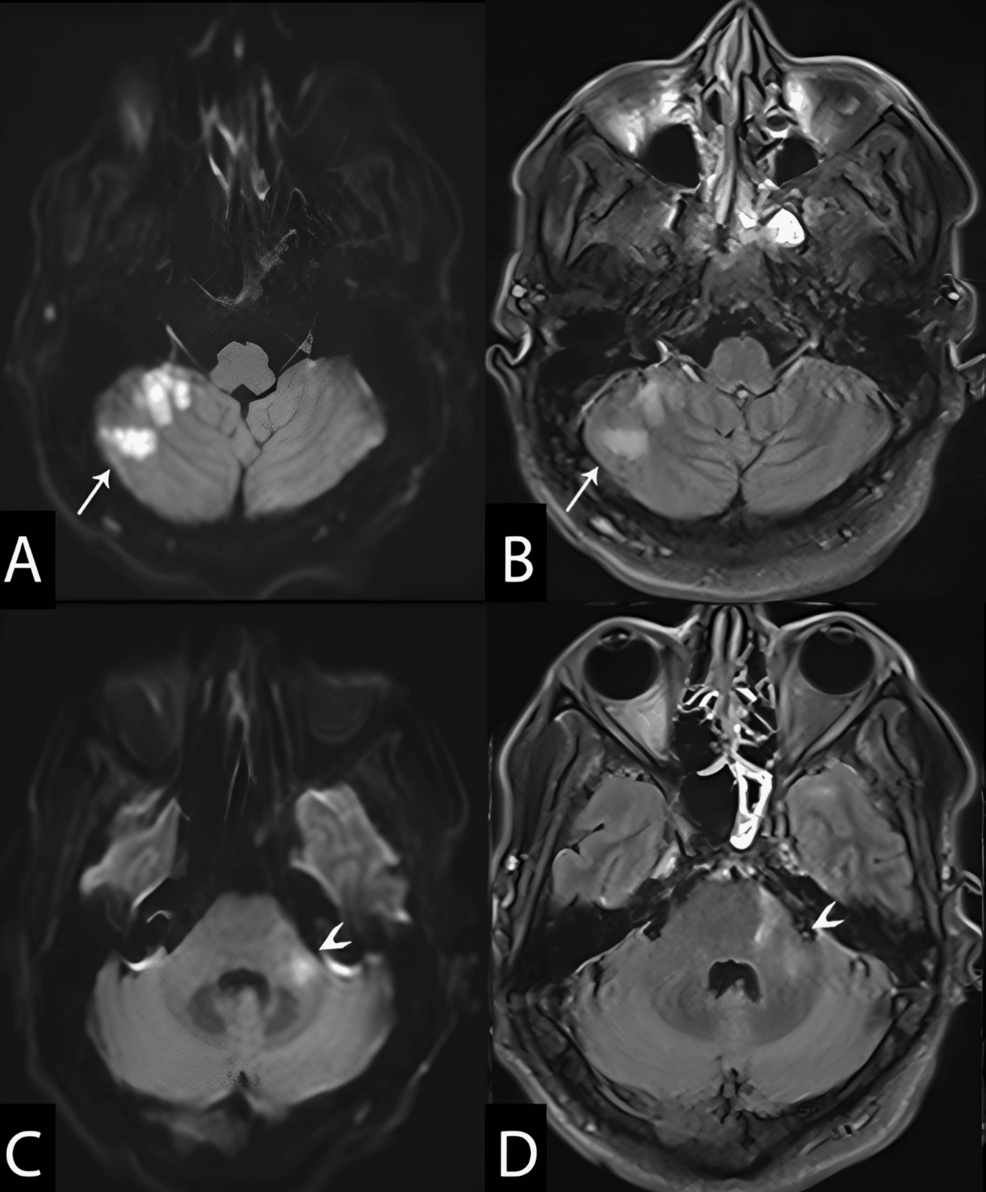

Diagnosing viral-induced CNS vasculitis can be a lengthy process, often involving advanced imaging techniques like MRI and MRA, and also cerebrospinal fluid analysis. The treatment typically involves a combination of antiviral medications and immunosuppressants or anti-inflammatory drugs, carefully balanced to manage the specific viral triggers while supporting the patient’s immune status.